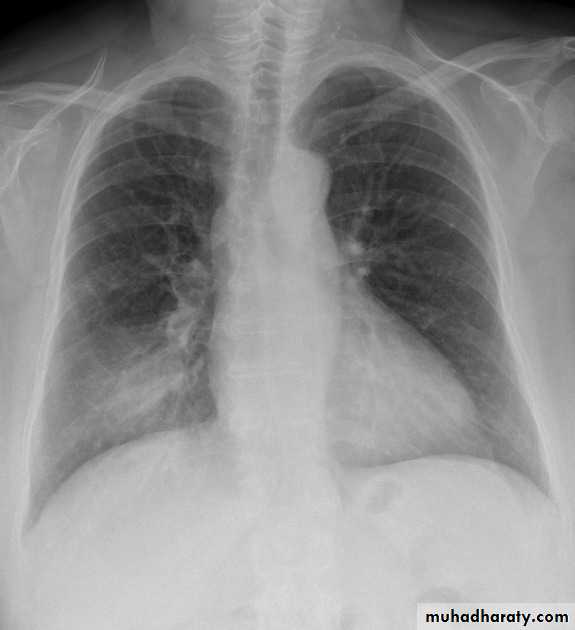

Pleural effusion

SubpulmonaryOn the frontal film, the highest point of the apparent right hemi diaphragm is displaced laterally (it is usually in the center).

Blunting of CP angle

Normally there are 2-10cc of fluid in the pleural spaceWhen >75cc accumulate, the posterior costophrenic (CP) sulci, seen on the lateral film, become blunted

When 200-300cc accumulate, the CP sulci on the frontal film become blunted

Meniscus sign

Pleural fluid tends to rise higher along its edge producing a meniscus shape medially and laterallyUsually only lateral meniscus can be seen

The meniscus is a good indicator of the presence of a pleural effusion